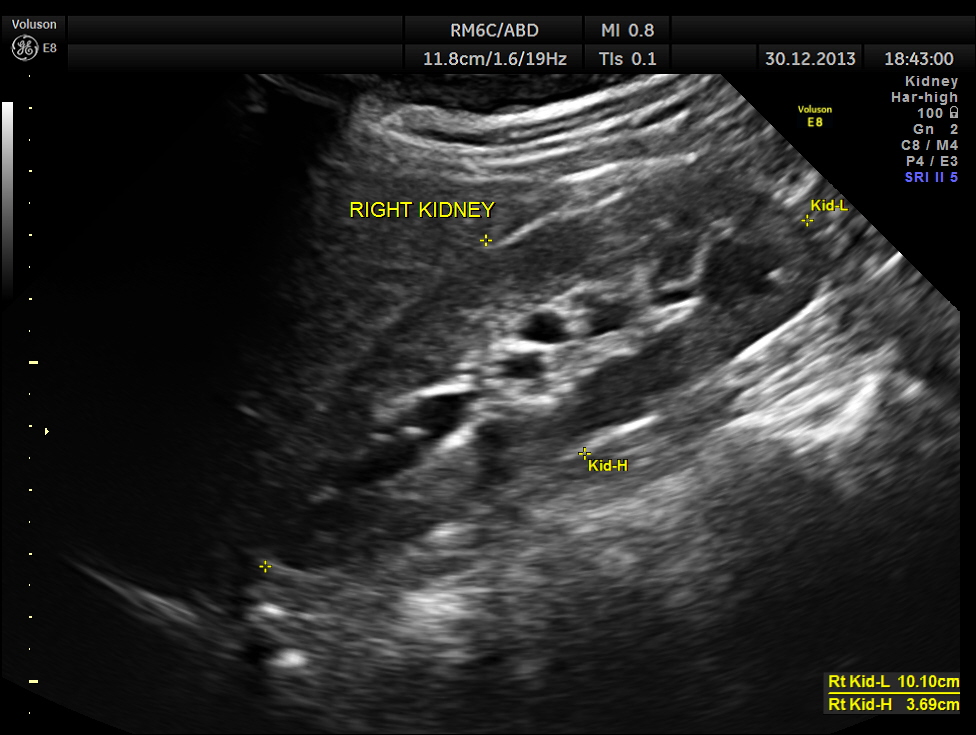

the kidneys were normal.